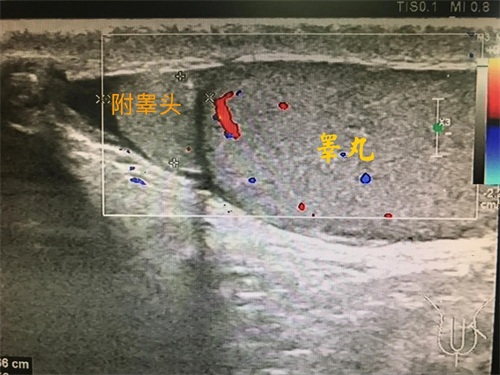

睾丸在超声下到底长啥样?

正常成年男性睾丸大小约长4CM、厚约2CM、宽约3CM,睾丸外面有一层包膜,内部为睾丸实质,回声均匀,内部会有稀疏的血量信号。影响睾丸大小的原因有:睾丸炎、睾丸肿瘤、睾丸囊肿等。还有就是睾丸的周围还趴着一个附睾,附睾也是生殖系统重要的器官之一,它分为头、体、尾部。

说那么多,我的睾丸一大一小到底有没有问题?其实两边睾丸本来就不是完全一样大,只要两边睾丸的大小差异不太大,都是在正常大小范围内,也就没什么问题的。如果睾丸大小差异明显,或者两个睾丸的大小达不到正常范围,这需要注意啦。到底是肿瘤或炎症引起的相对肿大,还是发育不良导致的小呢?有些病变直接影响精子的发育,导致影响受孕。这需要超声检查来测量和观察内部结果。

睾丸容积(ml)=睾丸长度(mm)×宽度(mm)×厚度(mm)×0.71,通常认为:生精功能正常的双侧睾丸超声下总容积至少20ml以上,而用Prader睾丸测量器总容积至少为30~35ml以上。